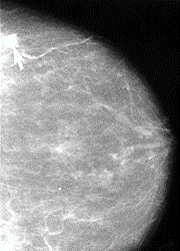

One of the most used tests is a screening mammogram. A mammogram is a low-dose x-ray. The x-ray picture shows your breast tissue including any abnormal areas. Mammograms cannot show if an abnormal area is cancer, but they can help your healthcare provider decide if you need more tests. You can only get a screening mammogram before you have symptoms. Once you have any symptoms you will need a diagnostic test.

Your mammogram report will also have information about your breast density, which is how much other tissue is in your breast compared to fatty tissue. Denser breasts make it harder to see abnormal areas on mammograms. It also slightly raises your risk of breast cancer.